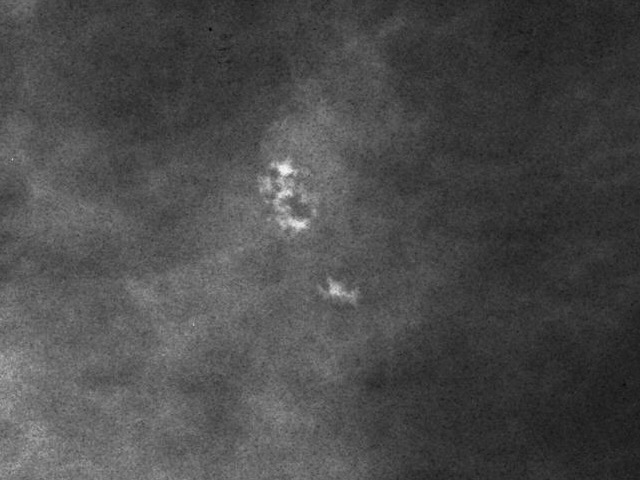

Bitte beurteilen Sie die Dignität

bösartig

gutartig